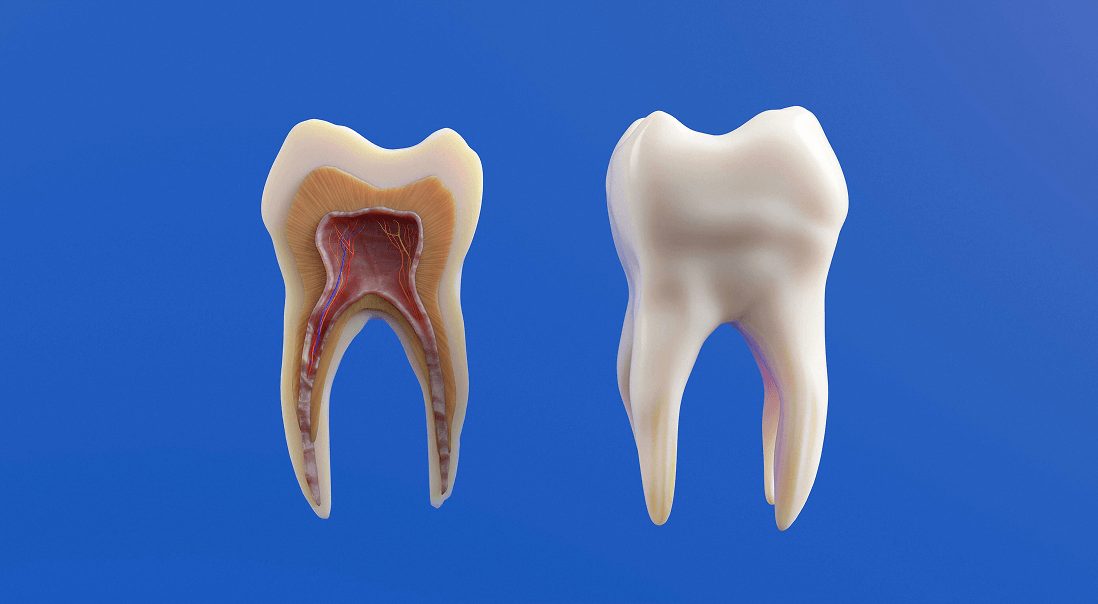

Na czym dokładnie polega leczenie endodontyczne? Zabieg leczenia kanałowego polega na usunięciu chorobowo zmienionej miazgi z komory oraz systemu kanałów zęba. Następnie kanały są dokładnie oczyszczane, dezynfekowane i szczelnie wypełniane specjalnym materiałem.

Zęby wraz z ich twardymi tkankami, oprócz pełnienia oczywistej dla wszystkich funkcji rozdrabniania pokarmu, ochraniają także usytuowane w kanale korzeniowym nerwy i naczynia krwionośne, czyli miazgę zębową.

Końcowa część korzenia, najwęższa i najbardziej oddalona od korony, to wierzchołek korzenia, przez który do kanału korzeniowego wnikają naczynia i nerwy. Następnie od wierzchołka przez całą długość korzenia biegną one do komory, gdzie tworzą miazgę zębową, która stanowi żywą strukturę zęba. Stany zapalne miazgi zęba, jako efekt próchnicy twardych tkanek, przenikają do okolicy i tkanek okołowierzchołkowych poprzez kanały zębowe. Przewlekły i bezobjawowy proces zapalny miazgi może być przyczyną chorób tkanek okołowierzchołkowych zęba. Choroby tych tkanek mogą mieć charakter niewielkich ziarniniaków, ale również rozległych torbieli zapalnych.